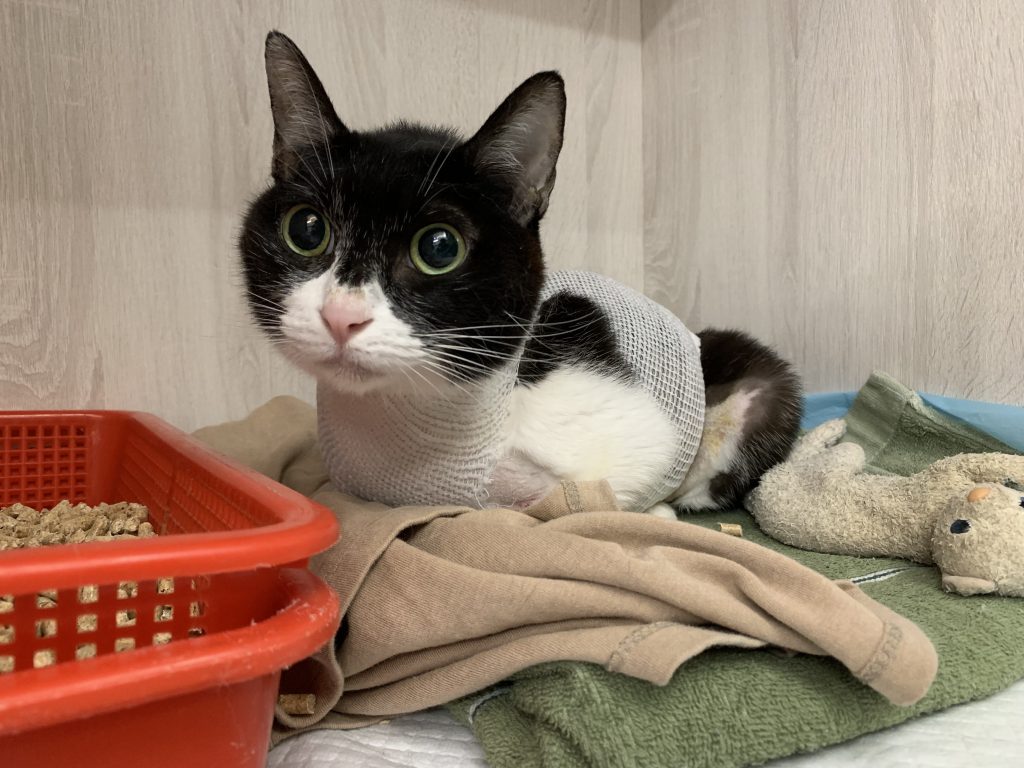

這張是手術後第24小時的照片,在良好止痛的幫助下,Kulo恢復得很順利。